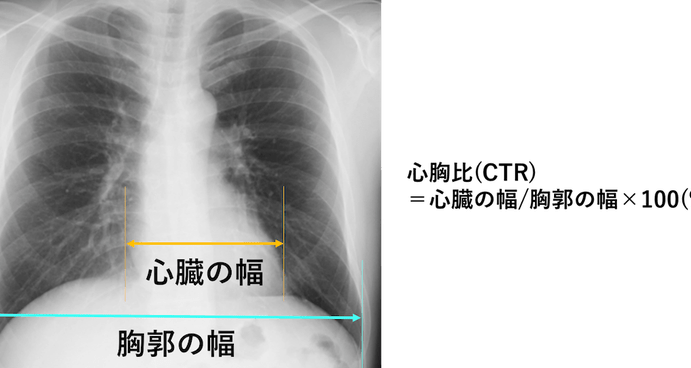

健康診断における心拡大の検査方法

健康診断で心拡大を評価する際、いくつかの検査方法が使用されます。これらの検査は、心臓のサイズや機能を詳しく把握するために重要です。